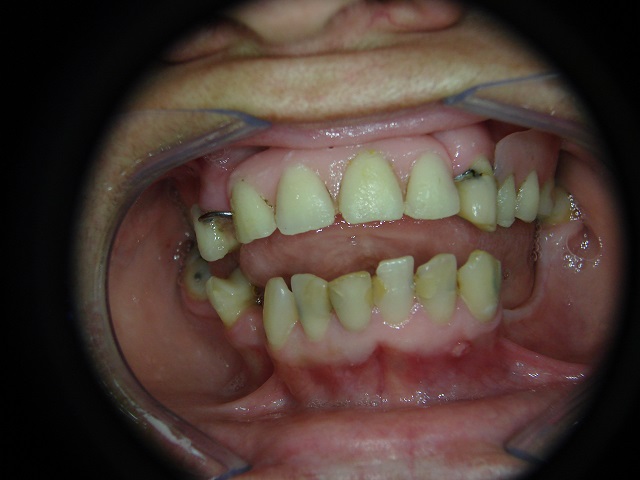

Caso Inicial